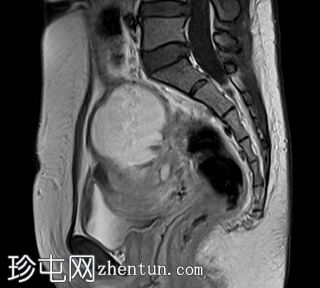

矢状位

7.jpg

T2加权像

左侧卵巢可见一巨大、无强化囊性病变。该病变壁薄,在T1加权像和T1脂肪抑制像上呈均匀高信号,在T2加权像上呈独特的阴影状,符合子宫内膜异位囊肿的特征。值得注意的是,该病变可见两个增强灶,但未见内部实性成分或对比增强。

子宫后壁子宫圆锥增厚,累及直肠前壁。

子宫、双侧卵巢和直肠因挛缩性粘连/纤维带而靠近,形成近期描述的深部盆腔子宫内膜异位症的“三叶草征”。

双侧卵巢出血性囊肿提示双侧子宫内膜异位囊肿,也称为巧克力囊肿。双侧卵巢位置接近,被称为“接吻卵巢”,这是由于粘连、子宫圆锥韧带和卵巢圆韧带增厚以及卵巢、直肠和子宫呈三叶草状排列所致,提示盆腔子宫内膜异位症。